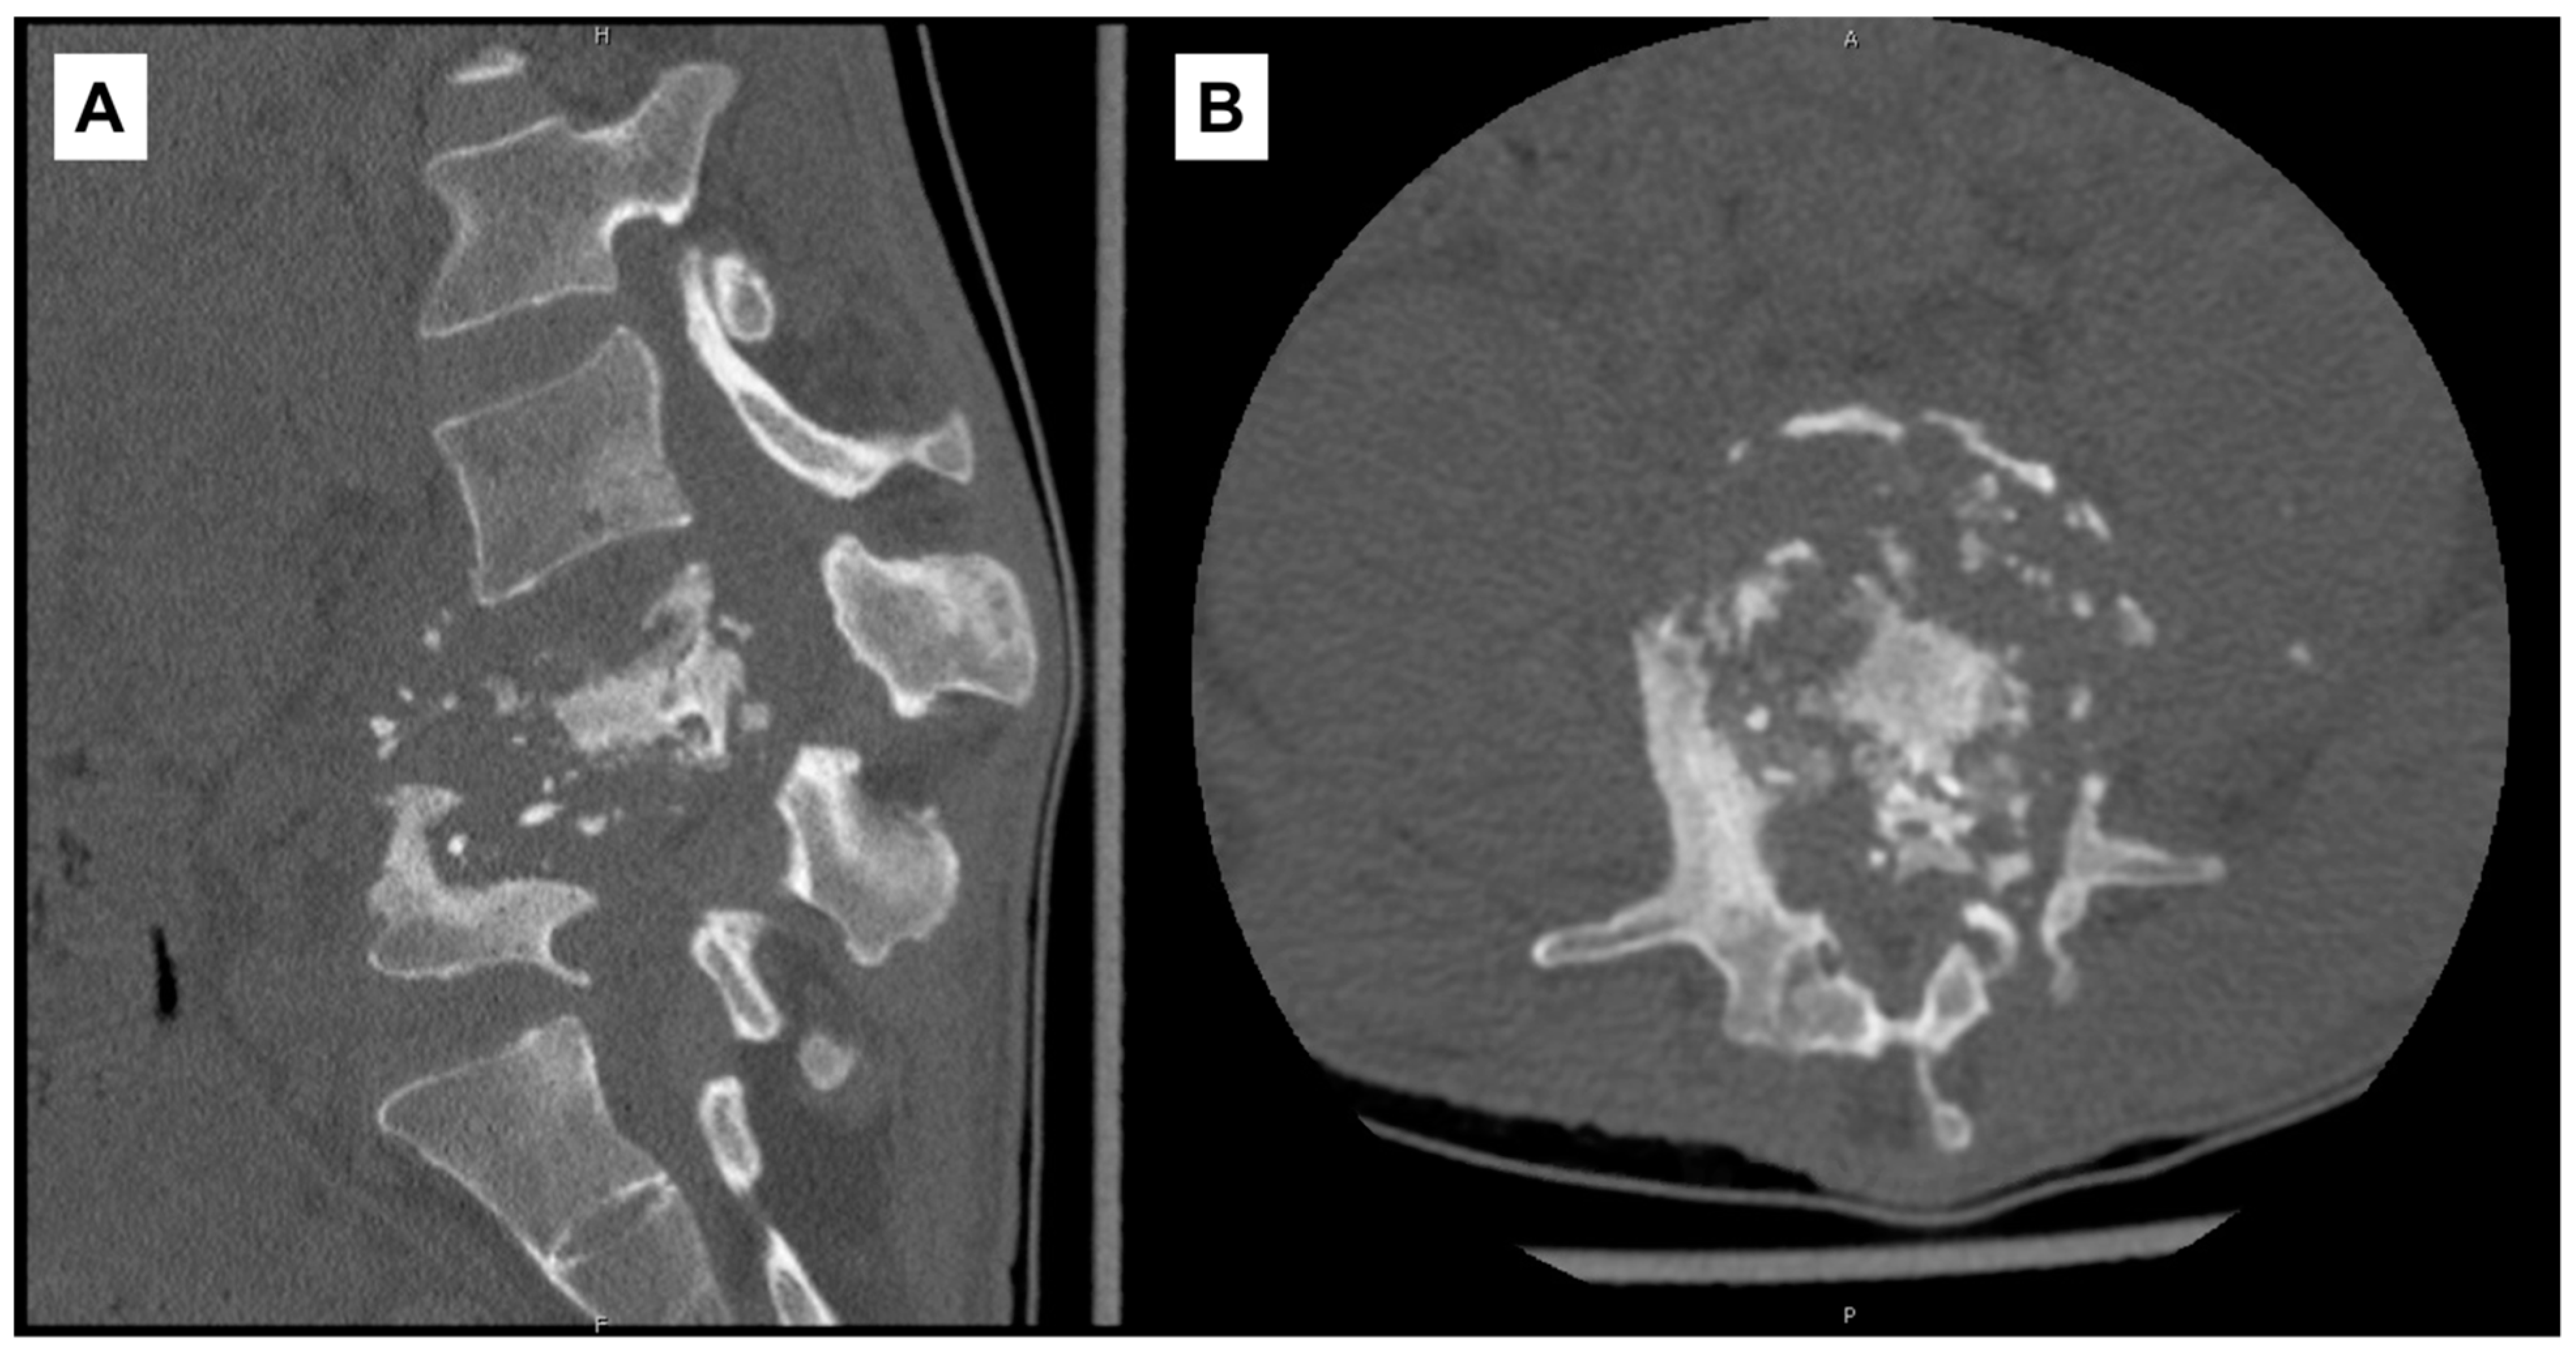

On admission to our institution, RIPE was continued and other antibiotics discontinued. Frank gibbus deformity and tenderness in the lumbar region were noted on exam. Laboratory studies showed leukocytosis (14,500/μL; ref. range: 4000–10,000/μL), anemia (9.2 g/dL), thrombocytosis (621 × 103/μL; ref. range: 140–440 × 103/μL), elevated hsCRP (178.6 mg/L), and elevated sedimentation rate (117 mm/hr). A repeat CT scan of the lumbar spine without contrast on HD2 re-demonstrated prior findings (Figure 2).

Three AFB sputum cultures were collected and eventually returned negative. Moxifloxacin was added to the treatment regimen on HD3 given concern for resistance due to recent LTBI treatment. A CT scan of the chest, abdomen, and pelvis was performed and showed bilateral iliopsoas abscesses tracking to bilateral inguinal regions.

A CT-guided biopsy of L4 vertebral body and left paraspinal abscess aspiration were performed on HD7. Specimens were sent for AFB staining, culture, pathology, and real-time PCR sequencing. Pathology of vertebral biopsy showed mild chronic osteomyelitis with negative AFB staining and no granulomatous inflammation. The left paraspinal abscess aspirate cultures ultimately grew MTB complex and coagulase-negative Staphylococcus in the following weeks, with the latter being deemed a contaminant. MTB complex DNA in the aspirate was also detected via real-time PCR. Bilateral inguinal collections were drained on HD9 by interventional radiology with the placement of three drainage catheters. Three separate specimens were sent for AFB culture, and one of three was smear-positive with 1+ AFB the following day. The specimen was sent to CT DPH for further testing. In subsequent weeks, all three cultures grew MTB complex.

Figure 2. Computed-tomography scan of lumbar spine with diffuse destruction of L4–L5 vertebral bodies. (A) Sagittal view. (B) Axial view at L4 vertebral level.